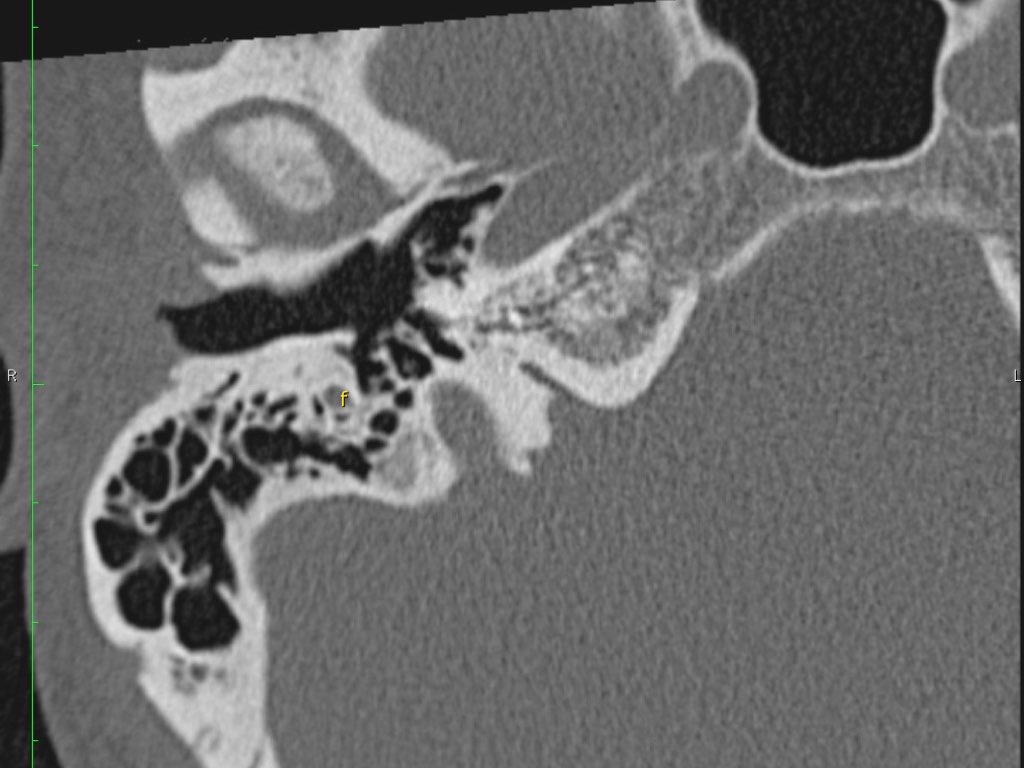

Trong bài tổng quan này, chúng tôi trình bày giải phẫu bình thường trên mặt phẳng cắt ngang (axial) và mặt phẳng cắt đứng ngang (coronal) của xương thái dương thông qua việc duyệt qua các hình ảnh.

Giải phẫu xương đá trên mặt phẳng cắt ngang (Axial)

Nhấp vào hình ảnh để phóng to.

Cuộn qua các hình ảnh.